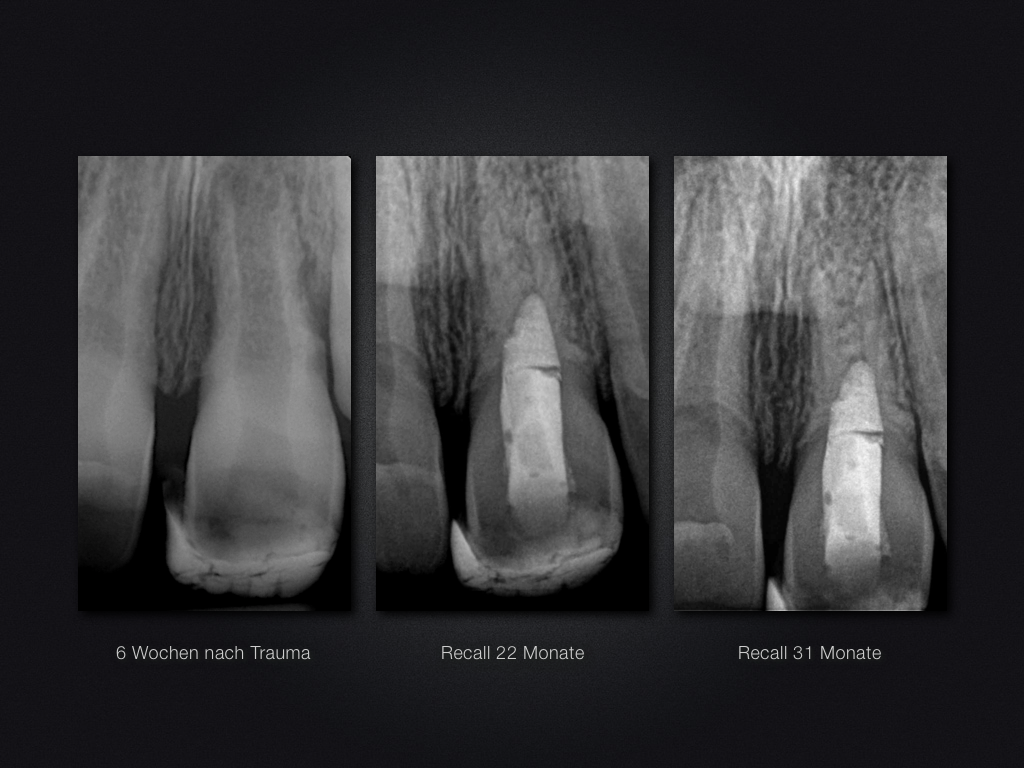

Praxistauglicher Kompromiss